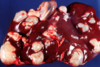

Tissue from sheep fetus

A

Multifocal necrotizing hepatitis

Campylobacter fetus fetus or C. jejuni